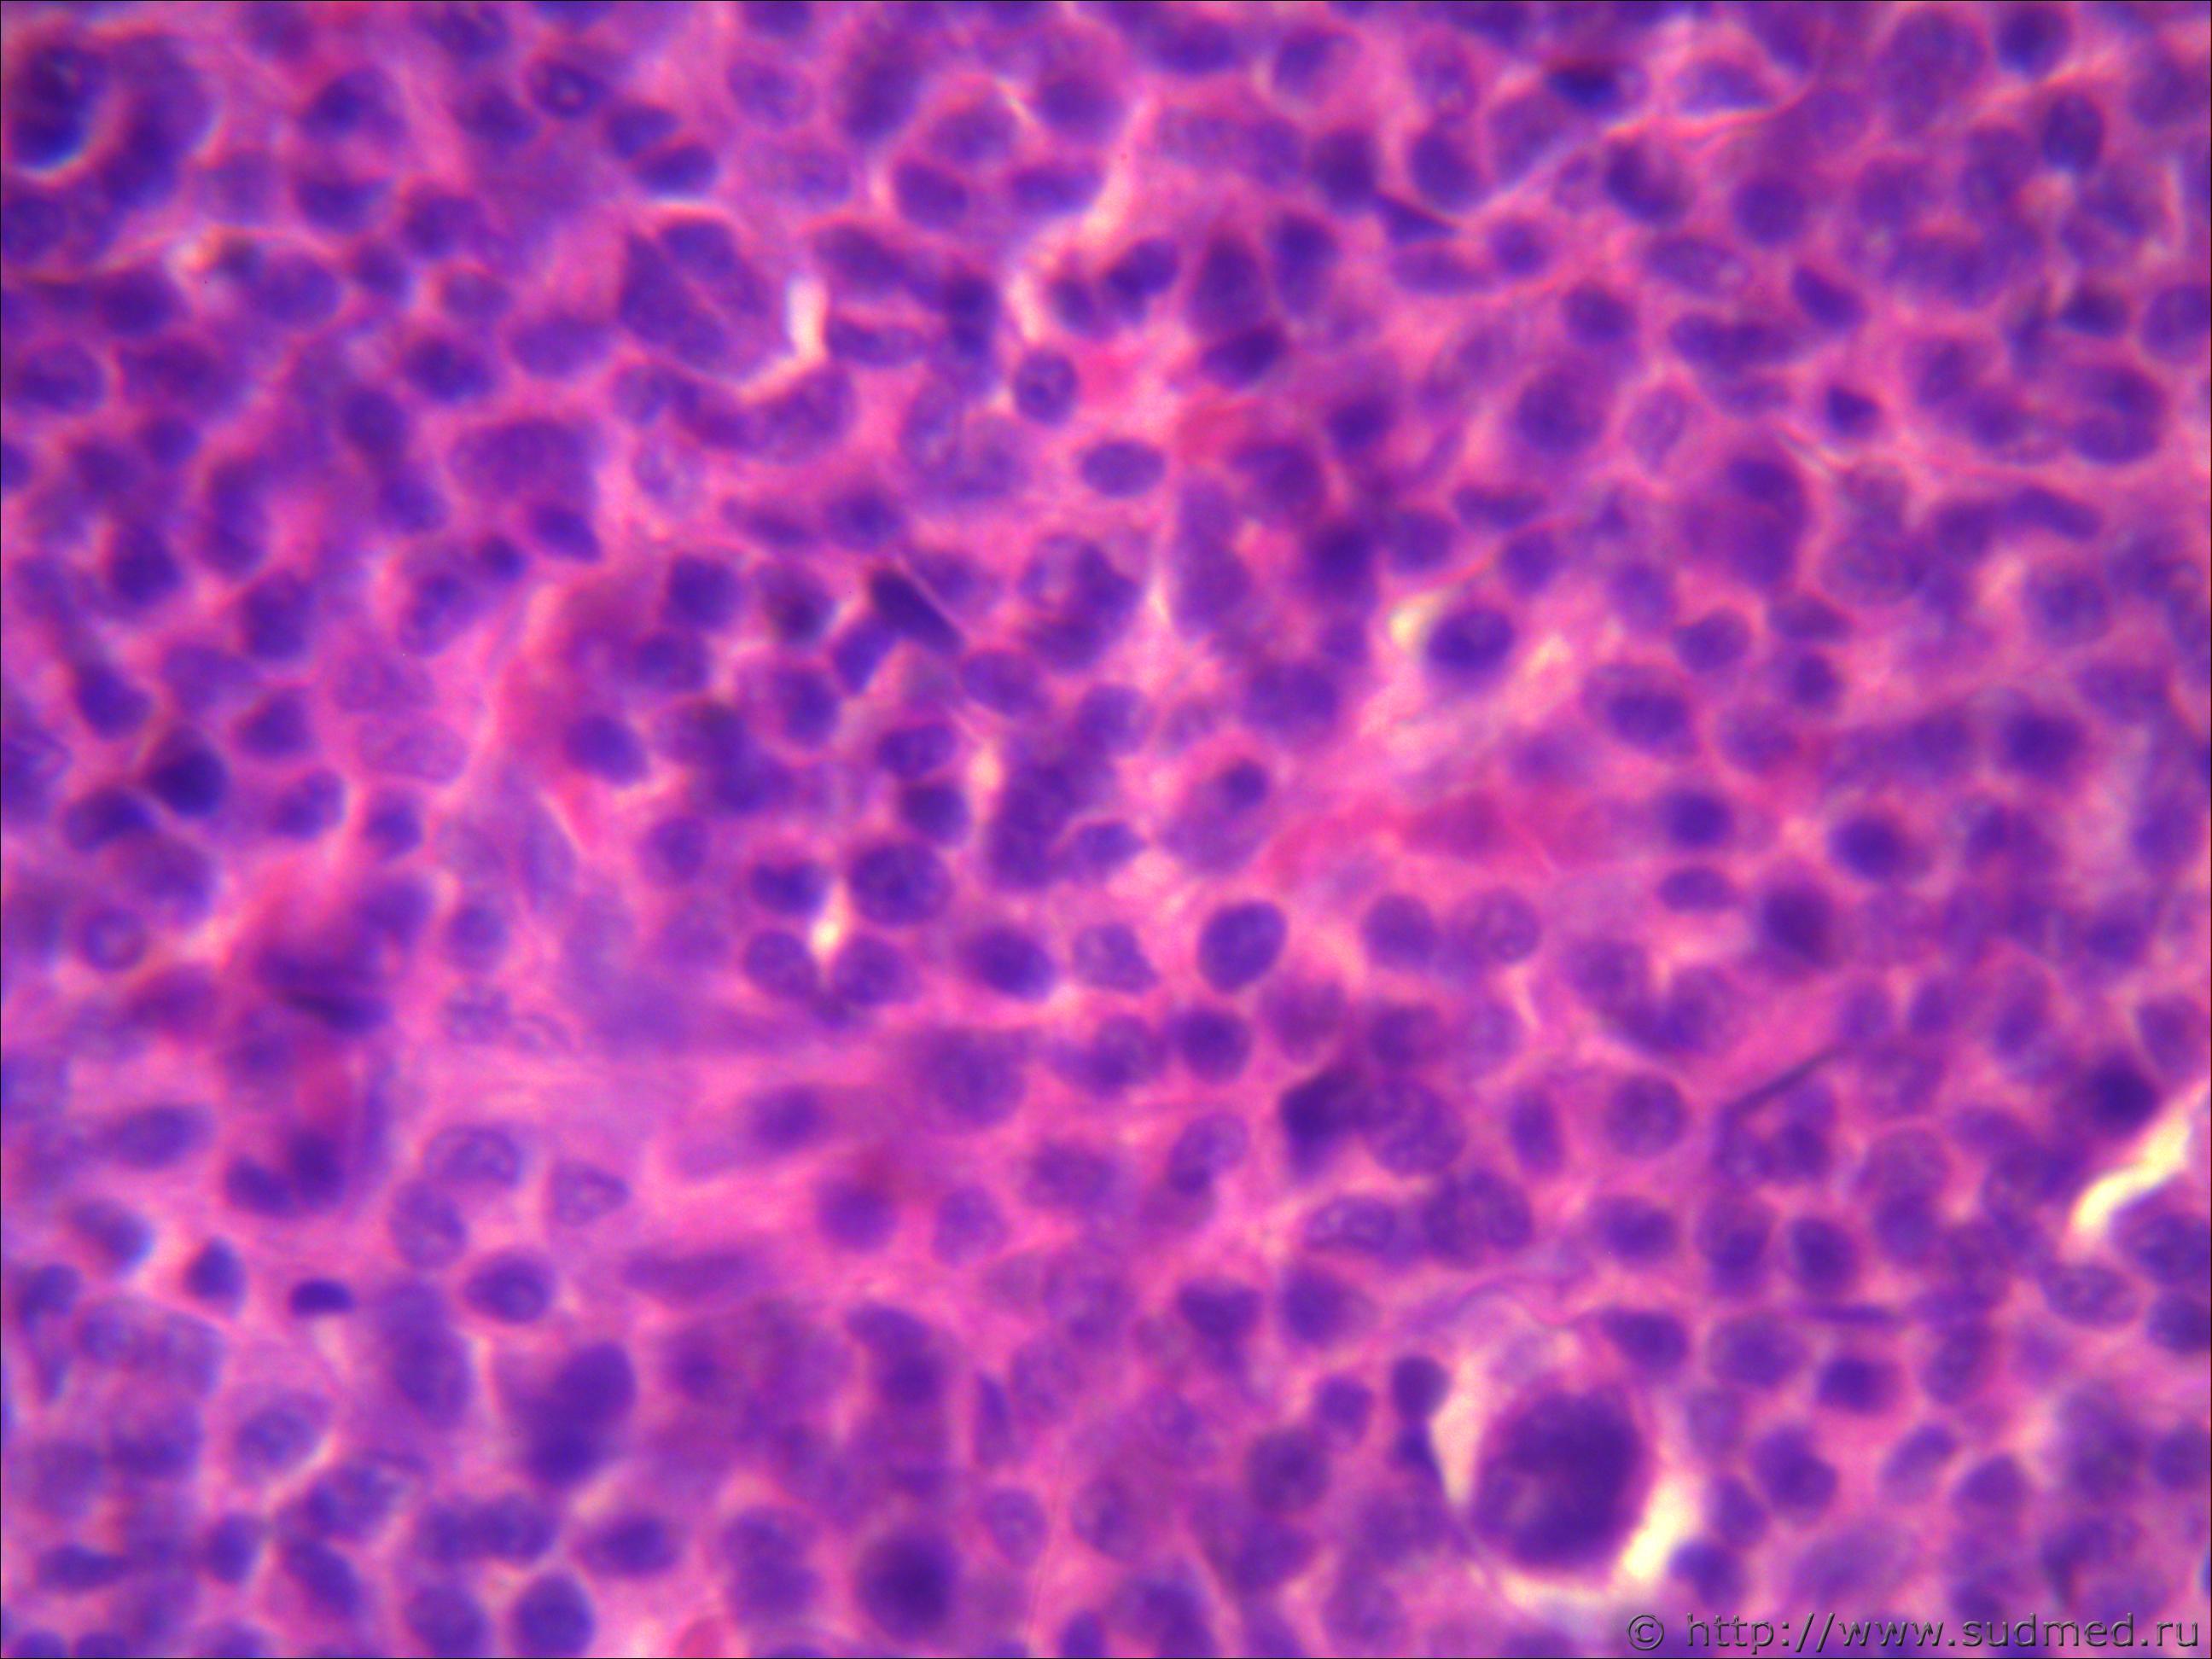

Н/о молочной железы

Похоже на беспигментную меланому.

Похоже на грибовидный микоз, либо на лимфоцитому(это мое мнение). В базальных клетках эпидермиса (на малом увеличении, где эпидермис четко ограничен)все таки меланомные пигменты видны, но без нарушения. Но видите как то резкости нет на фото.